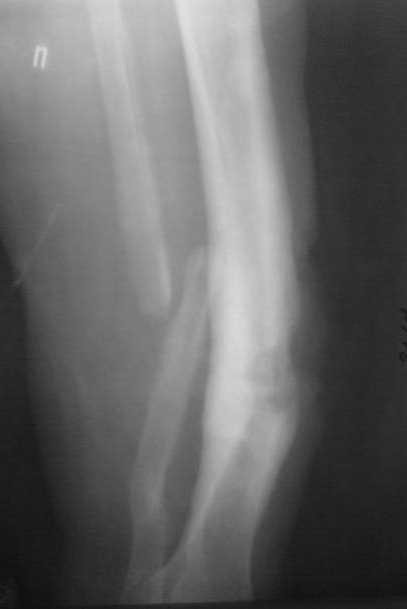

Сегодня принял больную, женщина 51 года. Травма автодорожная 13 лет назад. Тогда же - остеосинтез левого бедра стержнем (сращение);

ампутация левой голени на уровне с/3 (опротезирована); открытый перелом с/3 костей правой голени (лечение в аппарате Илизарова). Три года назад появился свищ на передней поверхности голени, лечилась нерегулярно и на сегодняшний момент вот такая картина. Перед госпитализацией, без назначения врача принимала тетрациклин в течение 10 дней.

Взяли посев, заказали дополнительные снимки, перевязка. Правый коленный сустав - движения с полной амплитудой. Частичная нагрузка на правую ногу при ходьбе. Пульсация на a. d. pedis сохранена, стопа теплая. Не температурит. Общее состояние удовлетворительное. Рана с обильным гнойным отделяемым со зловонным запахом на фоне гипергрануляций. Из свища определяю геморрагическое отделяемое.

Снимок месячной давности. Фистулография запланирована на след. неделю.

Планируем: коррекция оси в аппарате, дебридмент, резекция б/берцовой кости с острой копрессией для закрытия полости с бусами из цемента с а/б. Есть гадкое предчувствие, что "вылезет" MRSA на посеве. Надеюсь на помощь в тактике лечения данной пациентки у опытных коллег.